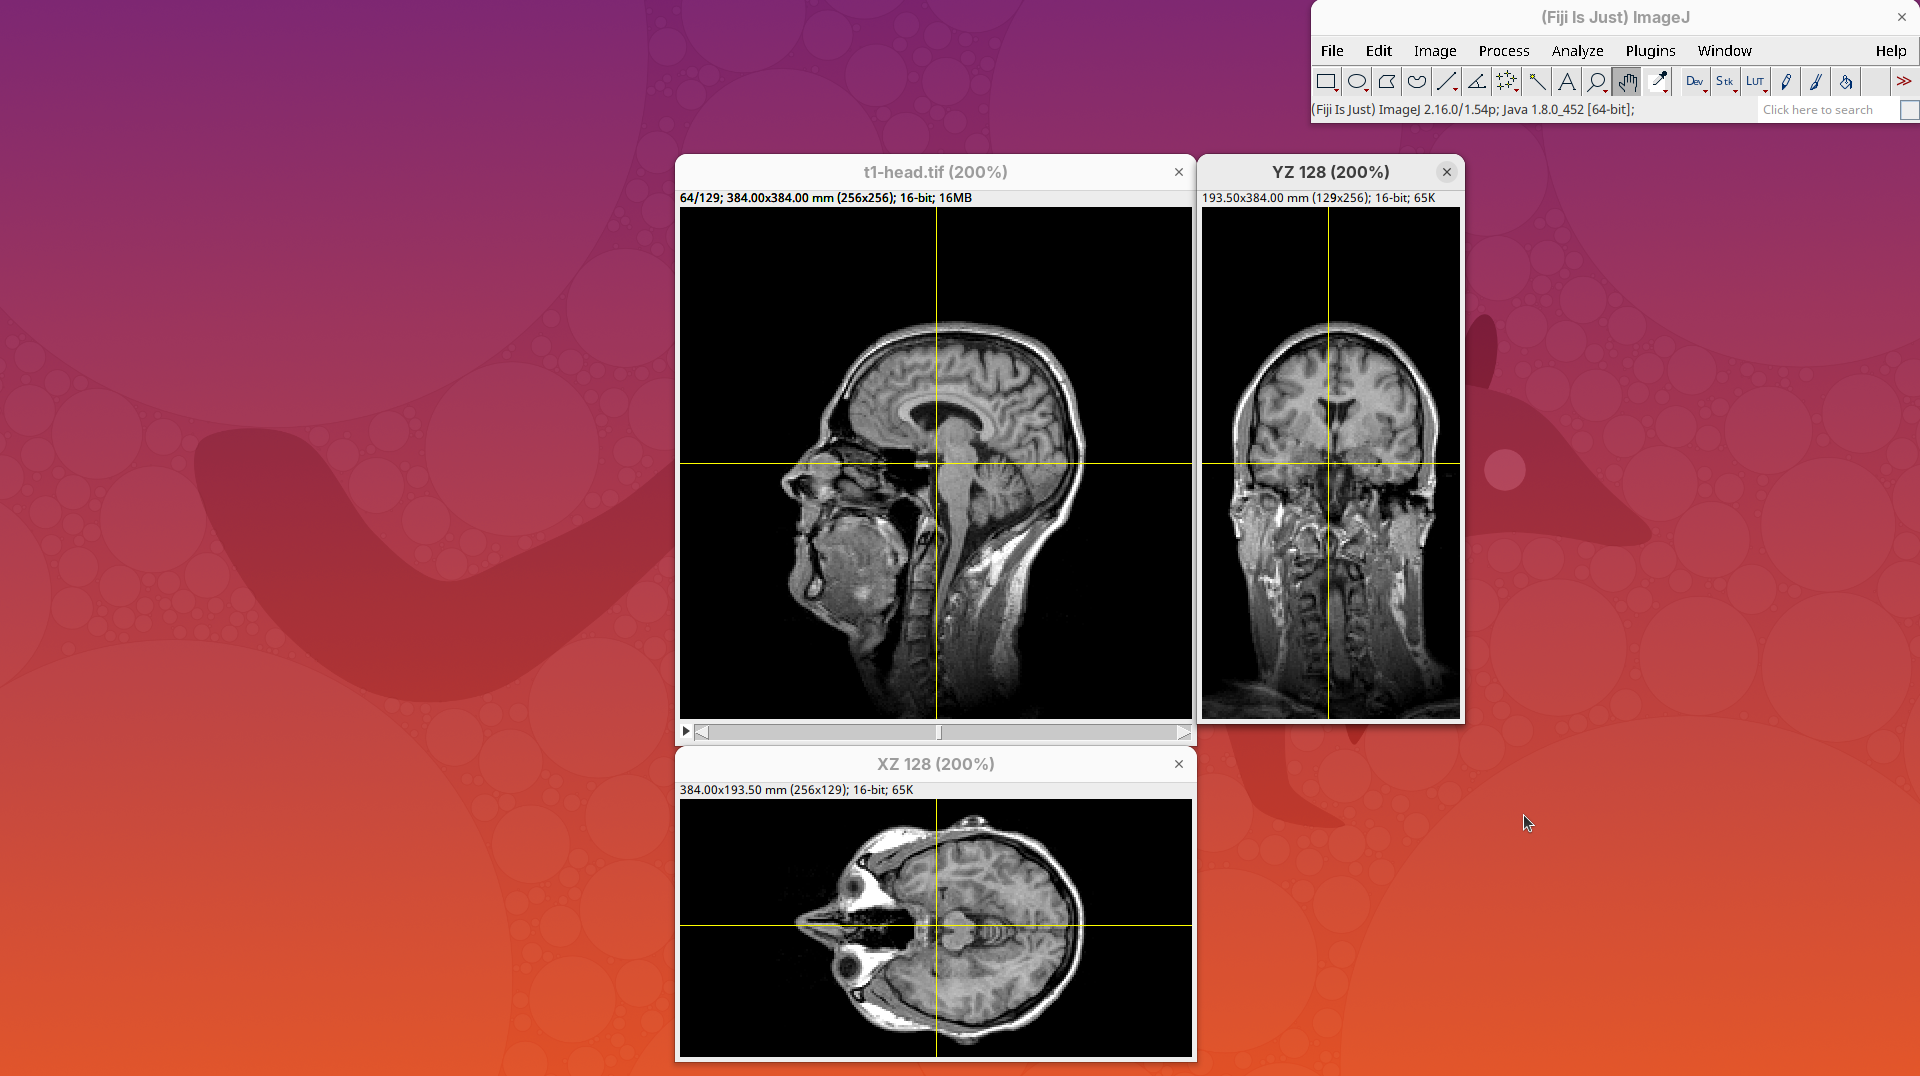

Orthogonal Views is a tool that shows the optical sections through the orthogonal planes of XY: XZ and YZ. It is an easy and quick way to get a sense of the tridimensionality of your dataset. Whenever I’m opening a dataset for the first time I use Orthogonal Views. To activate it:

- Click on

Image>Stacks>Orthogonal Views(or pressCtrl+Shift+H). - The XZ and YZ panels will open next to your XY stack.

- The yellow lines are synchronized between the panels.

- Click around the different parts of the head to inspect the same position under different angles.

Orthogonal Views is a great way to start understanding your 3D data.